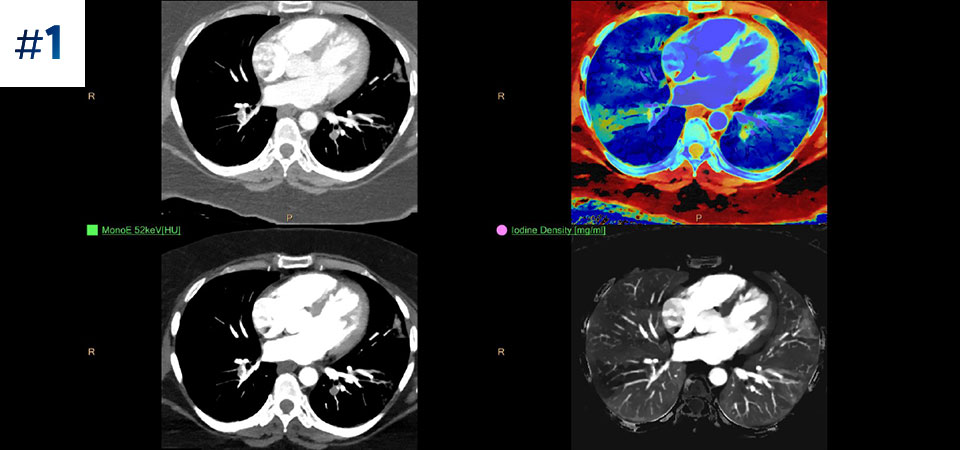

Dzięki nowym rozwiązaniom z zakresu obrazowania kardiologicznego i bezkompromisowemu podejściu do skanowania aparat Spectral CT 7500 pozwala uzyskać właściwe obrazy za pierwszym razem.

Pełna dostępność Pełne dane spektralne w każdym momencie zapewniają dostęp do wyników na każde żądanie – nawet w ujęciu retrospektywnym.

Typowy przebieg badania Pojedyncze skanowanie zapewniające szybki dostęp do konwencjonalnych i spektralnych danych uzyskanych z użyciem niskiej dawki — za każdym razem i w przypadku każdego pacjenta.

Nie ograniczaj się do konwencjonalnej tomografii komputerowej. Zobacz, jak wyniki uzyskane dzięki warstwom detektora spektralnego mogą zwiększyć pewność diagnostyczną.